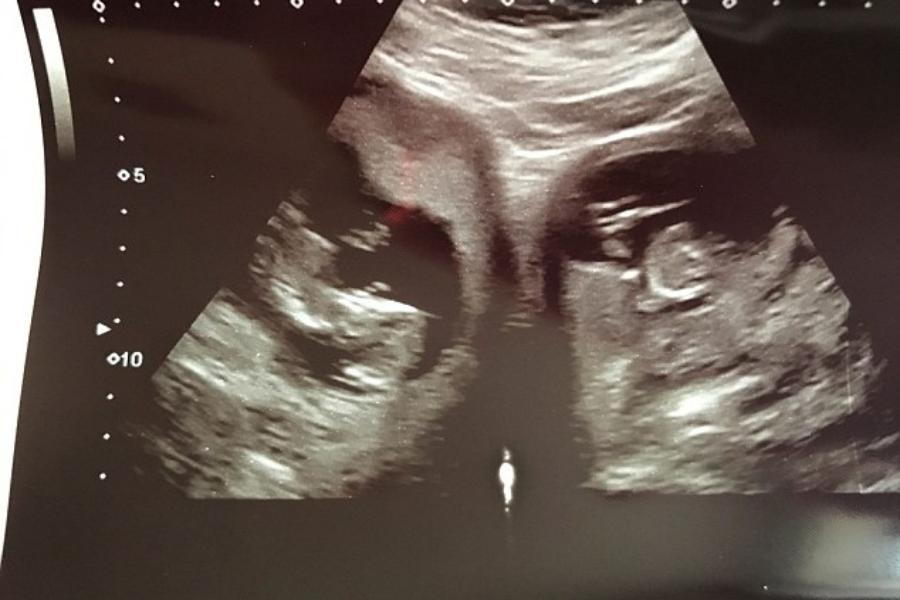

जेनिफर (31) और उनके पति एन्ड्रयू की पहले ही एक बेटी है, जिसका नाम मिली (8) है। जेनिफर ने बताया कि पिछली बार उनकी प्रेगनेंसी काफी साधारण थी, लेकिन इस बार सच्चाई का पता चलने पर उनके होश उड़ गए। उन्होंने बताया कि दो गर्भ की बात उन्हें प्रेगनेंसी के 20वें हफ्ते पता चली, जब वे अपनी जांच के लिए क्लिनिक आई थीं। जेनिफर ने इस बार प्रेगनेंसी के 34वें हफ्ते में एक साथ दो बच्चों को जन्म दिया है, जिनका नाम पॉपी (बेटी) और पिरान (बेटा) रखा गया है। जेनिफर की डिलीवरी सीज़ेरियन के ज़रिए हुई।